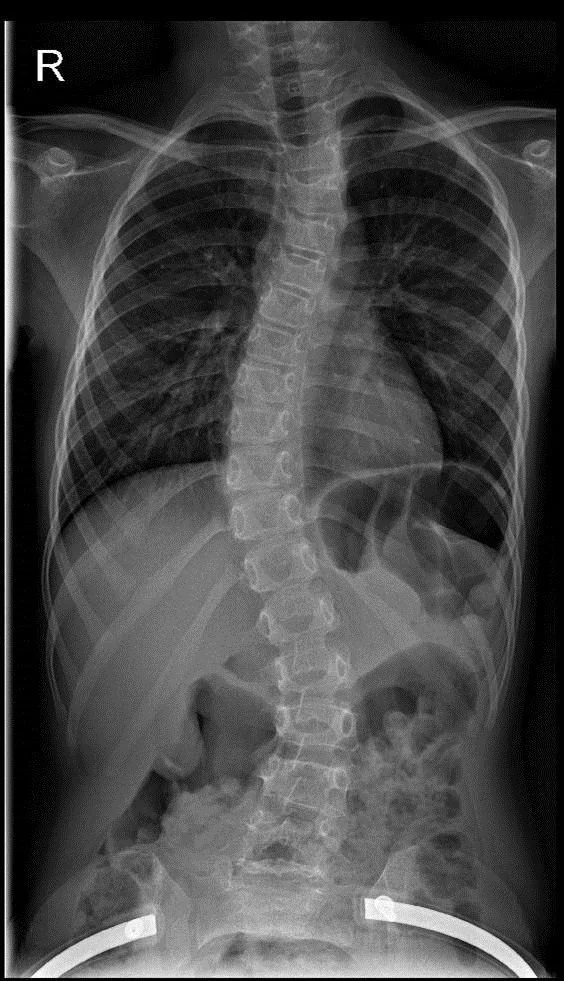

X-ray of the scoliotic spine

Scoliosis is usually a C- or S-shaped bend in the spine. The degree of curvature of the spine is measured by X-ray or computed tomography. If the curvature is mild, physiotherapy is the typical treatment. If the curvature is greater, a brace is used to try to correct it. In case of very strong curvatures of the spine, surgery has to be decided.